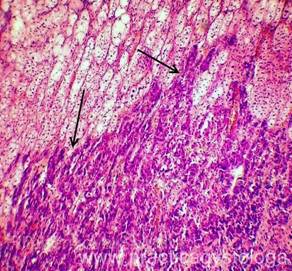

НАДПОЧЕЧНИК (1объект) - в срезах представлены преимущественно корковый слой надпочечника, небольшие фрагменты его мозгового слоя, в состоянии очагово-диффузного неравномерного капиллярно-венозного полнокровия, в ряде сосудов эритростазы, немногочисленные диапедезные микрогеморрагии. Неравномерно выраженная делипидизация цитоплазмы адренокортикоцитов клубочковой и пучковой зон коры. На границе коркового и мозгового слоёв надпочечника крупные очаги метастазов неороговевающего плоскоклеточного рака.

Рис. 4, 5. Метастазы плоскоклеточного неороговевающего рака лёгкого в правый и левый надпочечники (стрелки). Окраска: гематоксилин и эозин. Увеличение х100 и х250.